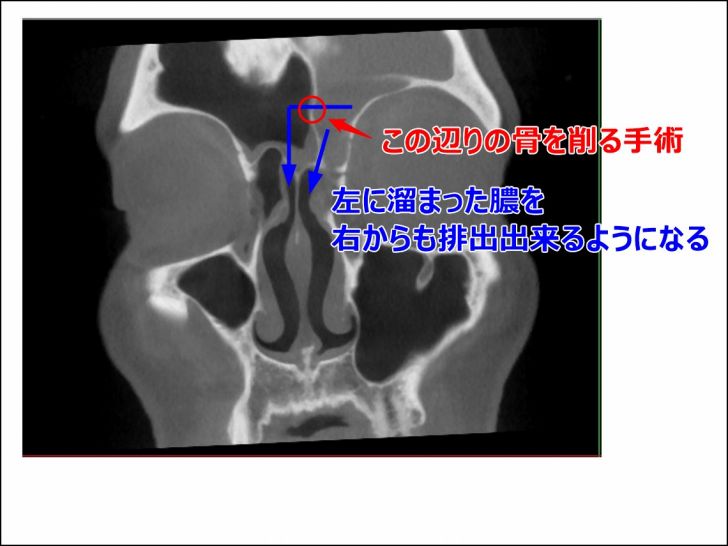

▼手術の概要はこんな感じ

画像に書いている通り、左右の前頭洞を隔てている骨を削る手術だそうです。

この手術を行うことで、左前頭洞に溜まった膿を右前頭洞にも流すことが出来るので、両方から膿を排出していけるようになるわけです。

鼻の穴から出来る手術のため、特に顔面に傷が残ることはないとのこと。